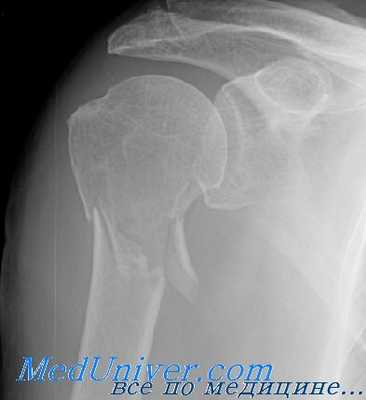

Серия рентгенограмм при повреждениях, рекомендованная Neer, очень помогает оценке переломов проксимального отдела плечевой кости. Кроме того, авторы рекомендуют снимки в переднезадней проекции с внутренней ротацией конечности и в аксиллярной проекции. Эти четыре проекции позволяют провести полную оценку плечевого сустава и проксимального отдела плечевой кости, включая суставную поверхность. Эти снимки можно делать больному в положении лежа, стоя или сидя, хотя авторы рекомендуют положение сидя.

Для уточнения диагноза назначают рентгенографию плечевого сустава в двух проекциях: прямой и «эполетной» (аксиальной). «Эполетный» снимок выполняют, отводя плечо от туловища под углом 30-40 градусов. Большее отведение категорически не рекомендуется, поскольку может усугубить смещение отломков. В сомнительных случаях используют КТ плечевого сустава. При подозрении на сдавление сосудисто-нервного пучка пациентов направляют на консультацию к неврологам или нейрохирургам и сосудистым хирургам.

Пациент предъявляет жалобы на боли в области плечевого сустава. Вколоченные переломы сопровождаются нерезким отеком, болезненностью при попытке активных движений. Пассивные движения ограничены незначительно. При переломе со смещением клиническая картина более яркая. Пострадавшего беспокоят выраженные боли. Выявляется умеренный отек, деформация области сустава и укорочение конечности. Определяется крепитация (хруст костных фрагментов). Диагноз уточняют по результатам рентгенографии. При внутрисуставном переломе может быть проведено УЗИ плечевого сустава.